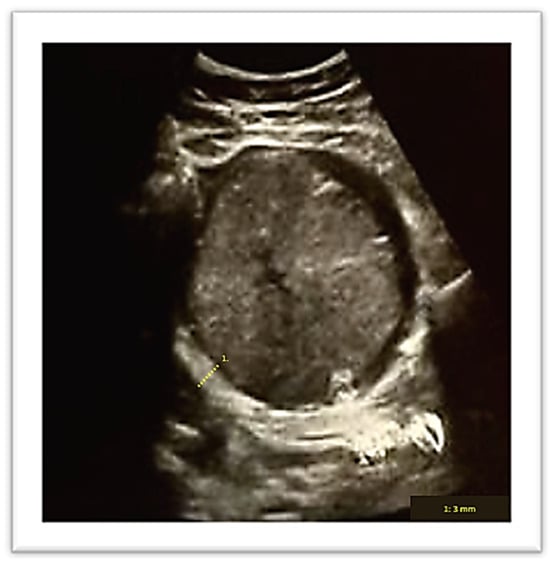

A vaginal delivery of a 2 kg male newborn occurred spontaneously after two days. The Apgar score at the 1st, 5th and 10th minute was, respectively, 10/10/10. Thirty minutes after delivery, despite active management of the third stage of labor, the placenta was still not delivered. An ultrasound evaluation showed the presence of an entangled placenta within the right uterine angle, and, according to Herman Ultrasound findings [12], the myometrium appeared thin at the placenta insertion but more than 2 mm (Figure 2), and there was no evidence of accreta spectrum.

Figure 2. Ultrasound evaluation of placenta location after birth. Number 1 demonstrates myometrial thickness measurement.